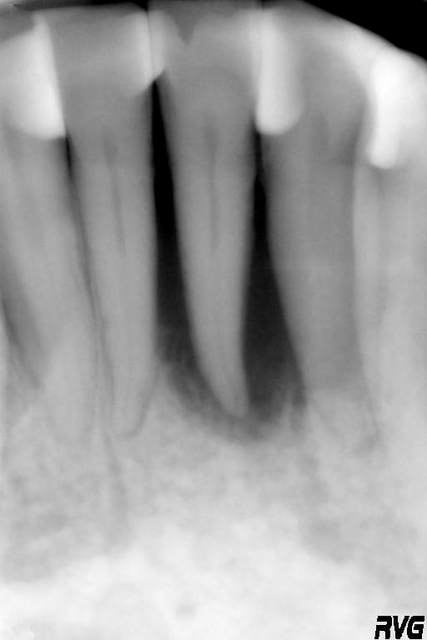

tiens je mets un second cas en mligne avant après et tu me diras ce qyue représente la petite image residuelle en mésial ....canal latéral ?

phil

19/09/2005 à 23h23

voici donc ce second cas ....